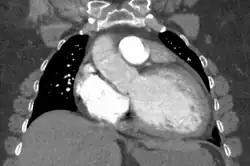

| Mouse heart slice showing dilated cardiomyopathy | |

Generalized enlargement of the heart is seen upon normal chest X-ray. Pleural effusion may also be noticed, which is due to pulmonary venous hypertension.[28]

The electrocardiogram often shows sinus tachycardia or atrial fibrillation, ventricular arrhythmias, left atrial enlargement, and sometimes intraventricular conduction defects and low voltage. When left bundle-branch block (LBBB) is accompanied by right axis deviation (RAD), the rare combination is considered to be highly suggestive of dilated or congestive cardiomyopathy.[29][30] Echocardiogram shows left ventricular dilatation with normal or thinned walls and reduced ejection fraction. Cardiac catheterization and coronary angiography are often performed to exclude ischemic heart disease.[28]

Cardiac magnetic resonance imaging (cardiac MRI) may also provide helpful diagnostic information in patients with dilated cardiomyopathy.[32]